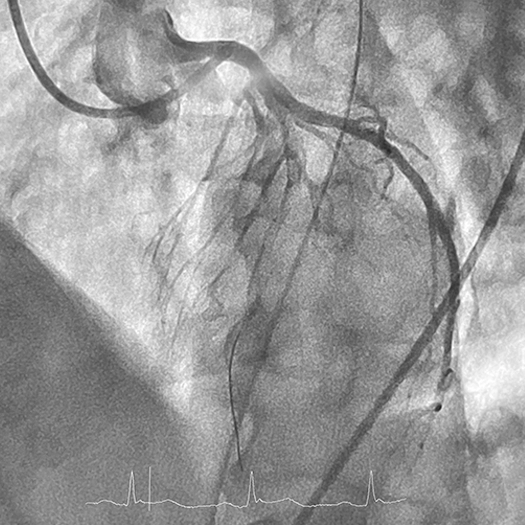

Upon arrival at the hospital, the patient was immediately taken to the catheterization lab. Initial angiography revealed total occlusion of the left anterior descending (LAD) artery, beginning in the proximal segment of the artery. The entire LAD was ladened with thrombus, extending all the way to the distal vessel. Dr. Hust suspected the patient had experienced a complete occlusion several hours earlier and had been accumulating thrombus since.

Angiogram of the left anterior descending (LAD) artery occluded with thrombus beginning in the proximal segment. Interventional wire can be seen coursing the LAD, defining the extent of thrombus. Angiogram of the left anterior descending (LAD) artery occluded with thrombus beginning in the proximal segment. Interventional wire can be seen coursing the LAD, defining the extent of thrombus.

Photo 1: Angiogram of the left anterior descending (LAD) artery occluded with thrombus beginning in the proximal segment. Interventional wire can be seen coursing the LAD, defining the extent of thrombus.